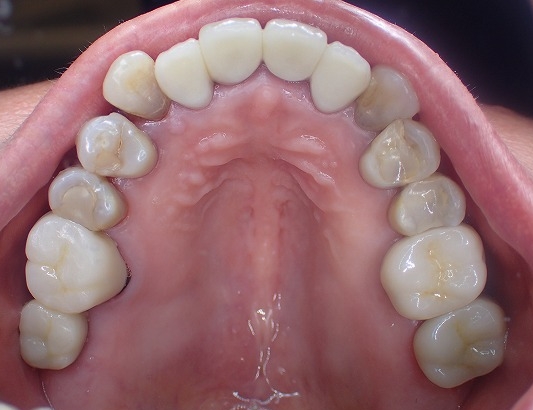

顔面に対して水平垂直も位置決めをして

左右対称に形態修正後、磨きをかけました。

よいものは長持ちです。

20年以上前の補綴物ですが綺麗になりました。

この方の場合は歯周病処置も含めて

定期的にお手入れすることがおすすめです。